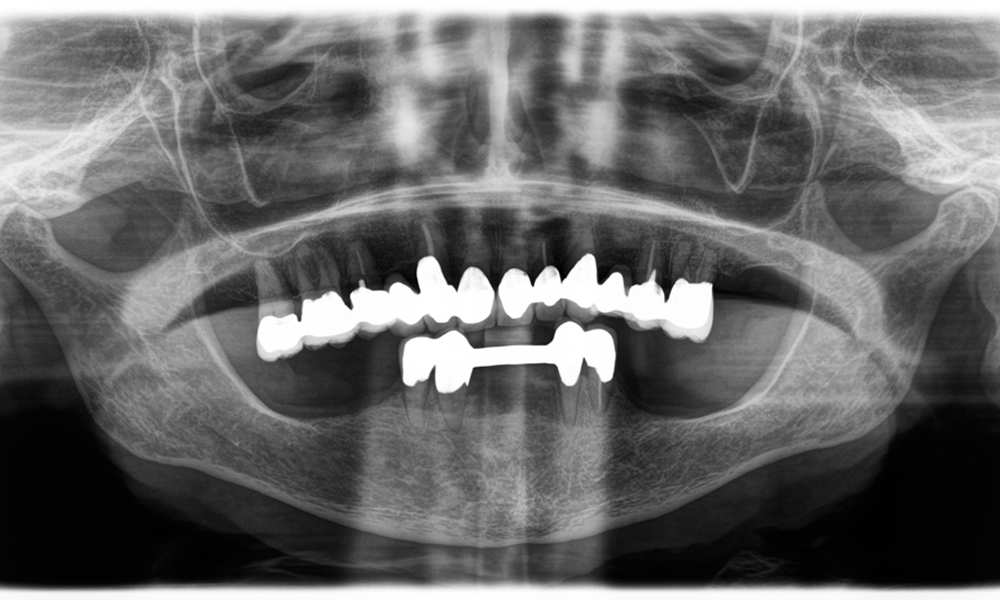

Dr. Wolfgang Tautschnig, ein erfahrener Zahnarzt aus Salzburg, hat die Synea Power Edition über mehrere Monate hinweg in seiner Praxis in verschiedenen klinischen Szenarien eingesetzt und evaluiert. Darunter vor allem für das Entfernen von Zirkonkronen und das Bearbeiten von unedlen Legierungen. In einem konkreten Fall stellte sich eine 81-jährige Patientin mit dem Wunsch nach einer ästhetischen Verbesserung ihrer 40 Jahre alten VMK-Kronen vor. Die bestehenden Kronen entsprachen nicht mehr den ästhetischen Ansprüchen der Patientin. Die Herausforderung lag in der Entfernung von zwölf verblockten Kronen mit unedler Legierung, ohne die darunterliegenden Zahnstümpfe zu beschädigen. Das Winkelstück wurde genutzt, um die Keramikschichten präzise einzuschlitzen sowie die Metallgerüste mit einem Hartmetallfräser zu trennen, um so die Kronen mit minimalem Trauma zu entfernen. Innerhalb von nur 30 Minuten waren die alten Kronen entfernt, danach konnte die neue Arbeit, bestehend aus Vollzirkon im Seitenzahnbereich und verblendeten Kronen im Frontzahnbereich, vorbereitet werden. Das Ergebnis war eine vollständige Neuanfertigung, die sowohl funktional als auch ästhetisch überzeugte (siehe Abb. 1).